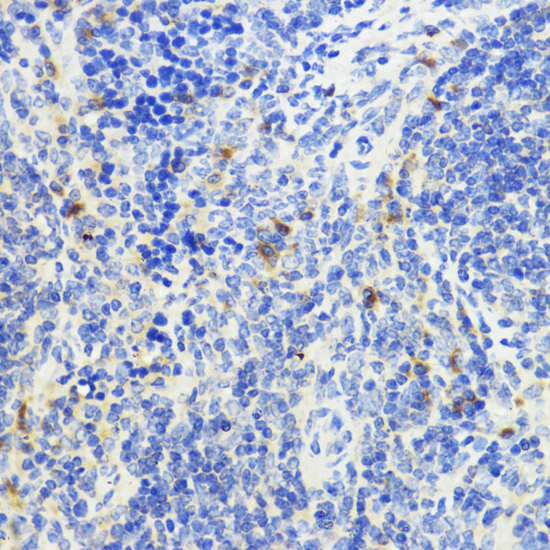

TD-502171-IHC-2.jpg

Immunohistochemistry analysis of paraffin-embedded mouse spleen using IL-10 antibody.High-pressure and temperature Sodium Citrate pH 6.0 was used for antigen retrieval.